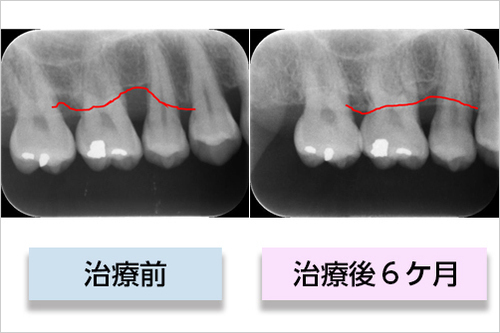

症例F(リグロスのみの症例)

• 行った治療の詳細

歯周組織再生療法(リグロス)

• 治療期間

7か月

• 治療にかかった費用

保険治療